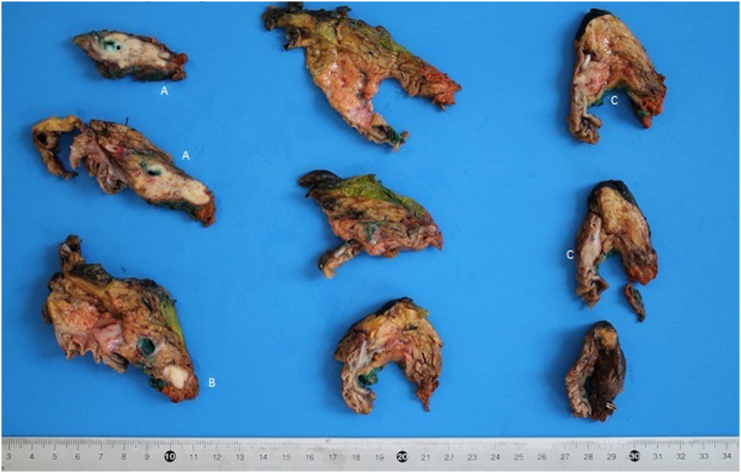

The patient underwent a Whipple’s cephalic duodenopancreatectomy, associated with a radical excision of gallbladder with hepatic resection of IVb and V segment, due to intraoperative suspicion of gallbladder cancer involving the CBD (Fig. 4). The intervention was performed by an expert surgeon specialized in hepatic, biliary and pancreatic surgery.

Final pathology report revealed the presence of three distinct cancers, respectively: moderated differentiated adenocarcinoma of gallbladder (Fig. 5) with invasion of cystic duct and hepatic tissue; moderately differentiated adenocarcinoma of mild CBD with serosa invasion (Fig. 6); Vater’s papilla moderately differentiated adenocarcinoma with sub-mucosal extension (Fig. 6). Gallbladder and CBD adenocarcinoma showed perineural and microvascular infiltration. Microscopic examination didn’t detect any direct continuity between the three tumors. Metastasis were identified in the pancreaticoduodenal, peri-hepatic and peri-gastric lymph nodes.